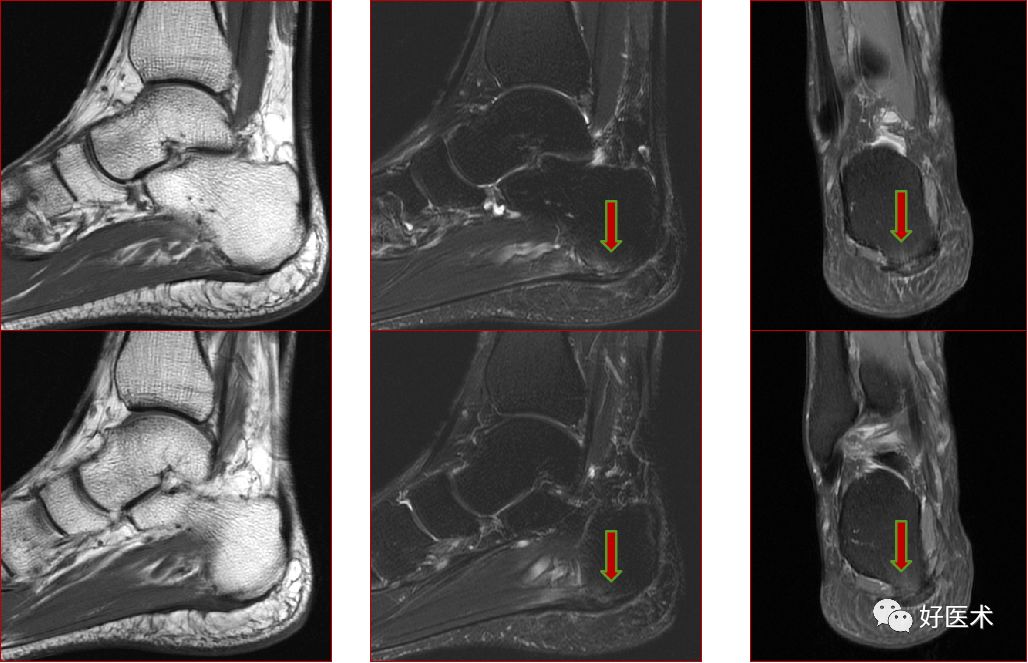

三、骨软骨病变

距骨骨软骨损伤,好发于前外侧、后内侧,尤其是后内侧,与内外翻损伤相关。

距骨骨软骨损伤分级

1度损伤:

2度损伤

3度损伤